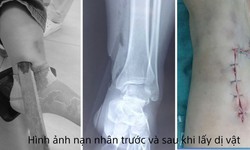

Đã xác minh được danh tính tài xế ô tô lao lên vỉa hè, tông gãy chân người phụ nữ rồi bỏ chạy

Xã hội - 16/03/2026 14:02

SKĐS - Qua xác minh, cơ quan công an xác định, tài xế điều khiển ô tô BKS 15K - 279.82 lao lên vỉa hè tông trúng người phụ nữ là anh N.X.T (SN 1978, trú tại phường Lê Ích Mộc, TP Hải Phòng)...